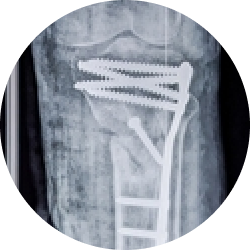

Доктор проводит сквозь всю толщу надколенника спицы Киршнера и затем закрепляет их проволокой.

Рана ушивается послойно, закрывается гипсовой повязкой или ортезом.

Хирургическая операция намного эффективнее других способов лечения. Благодаря ей, костные структуры прочно фиксируются в нужном положении. Кроме того, остеосинтез позволяет восстановить функции ноги, достичь стабильности колена, избежать вторичного смещения костных отломков и препятствует длительной иммобилизации.